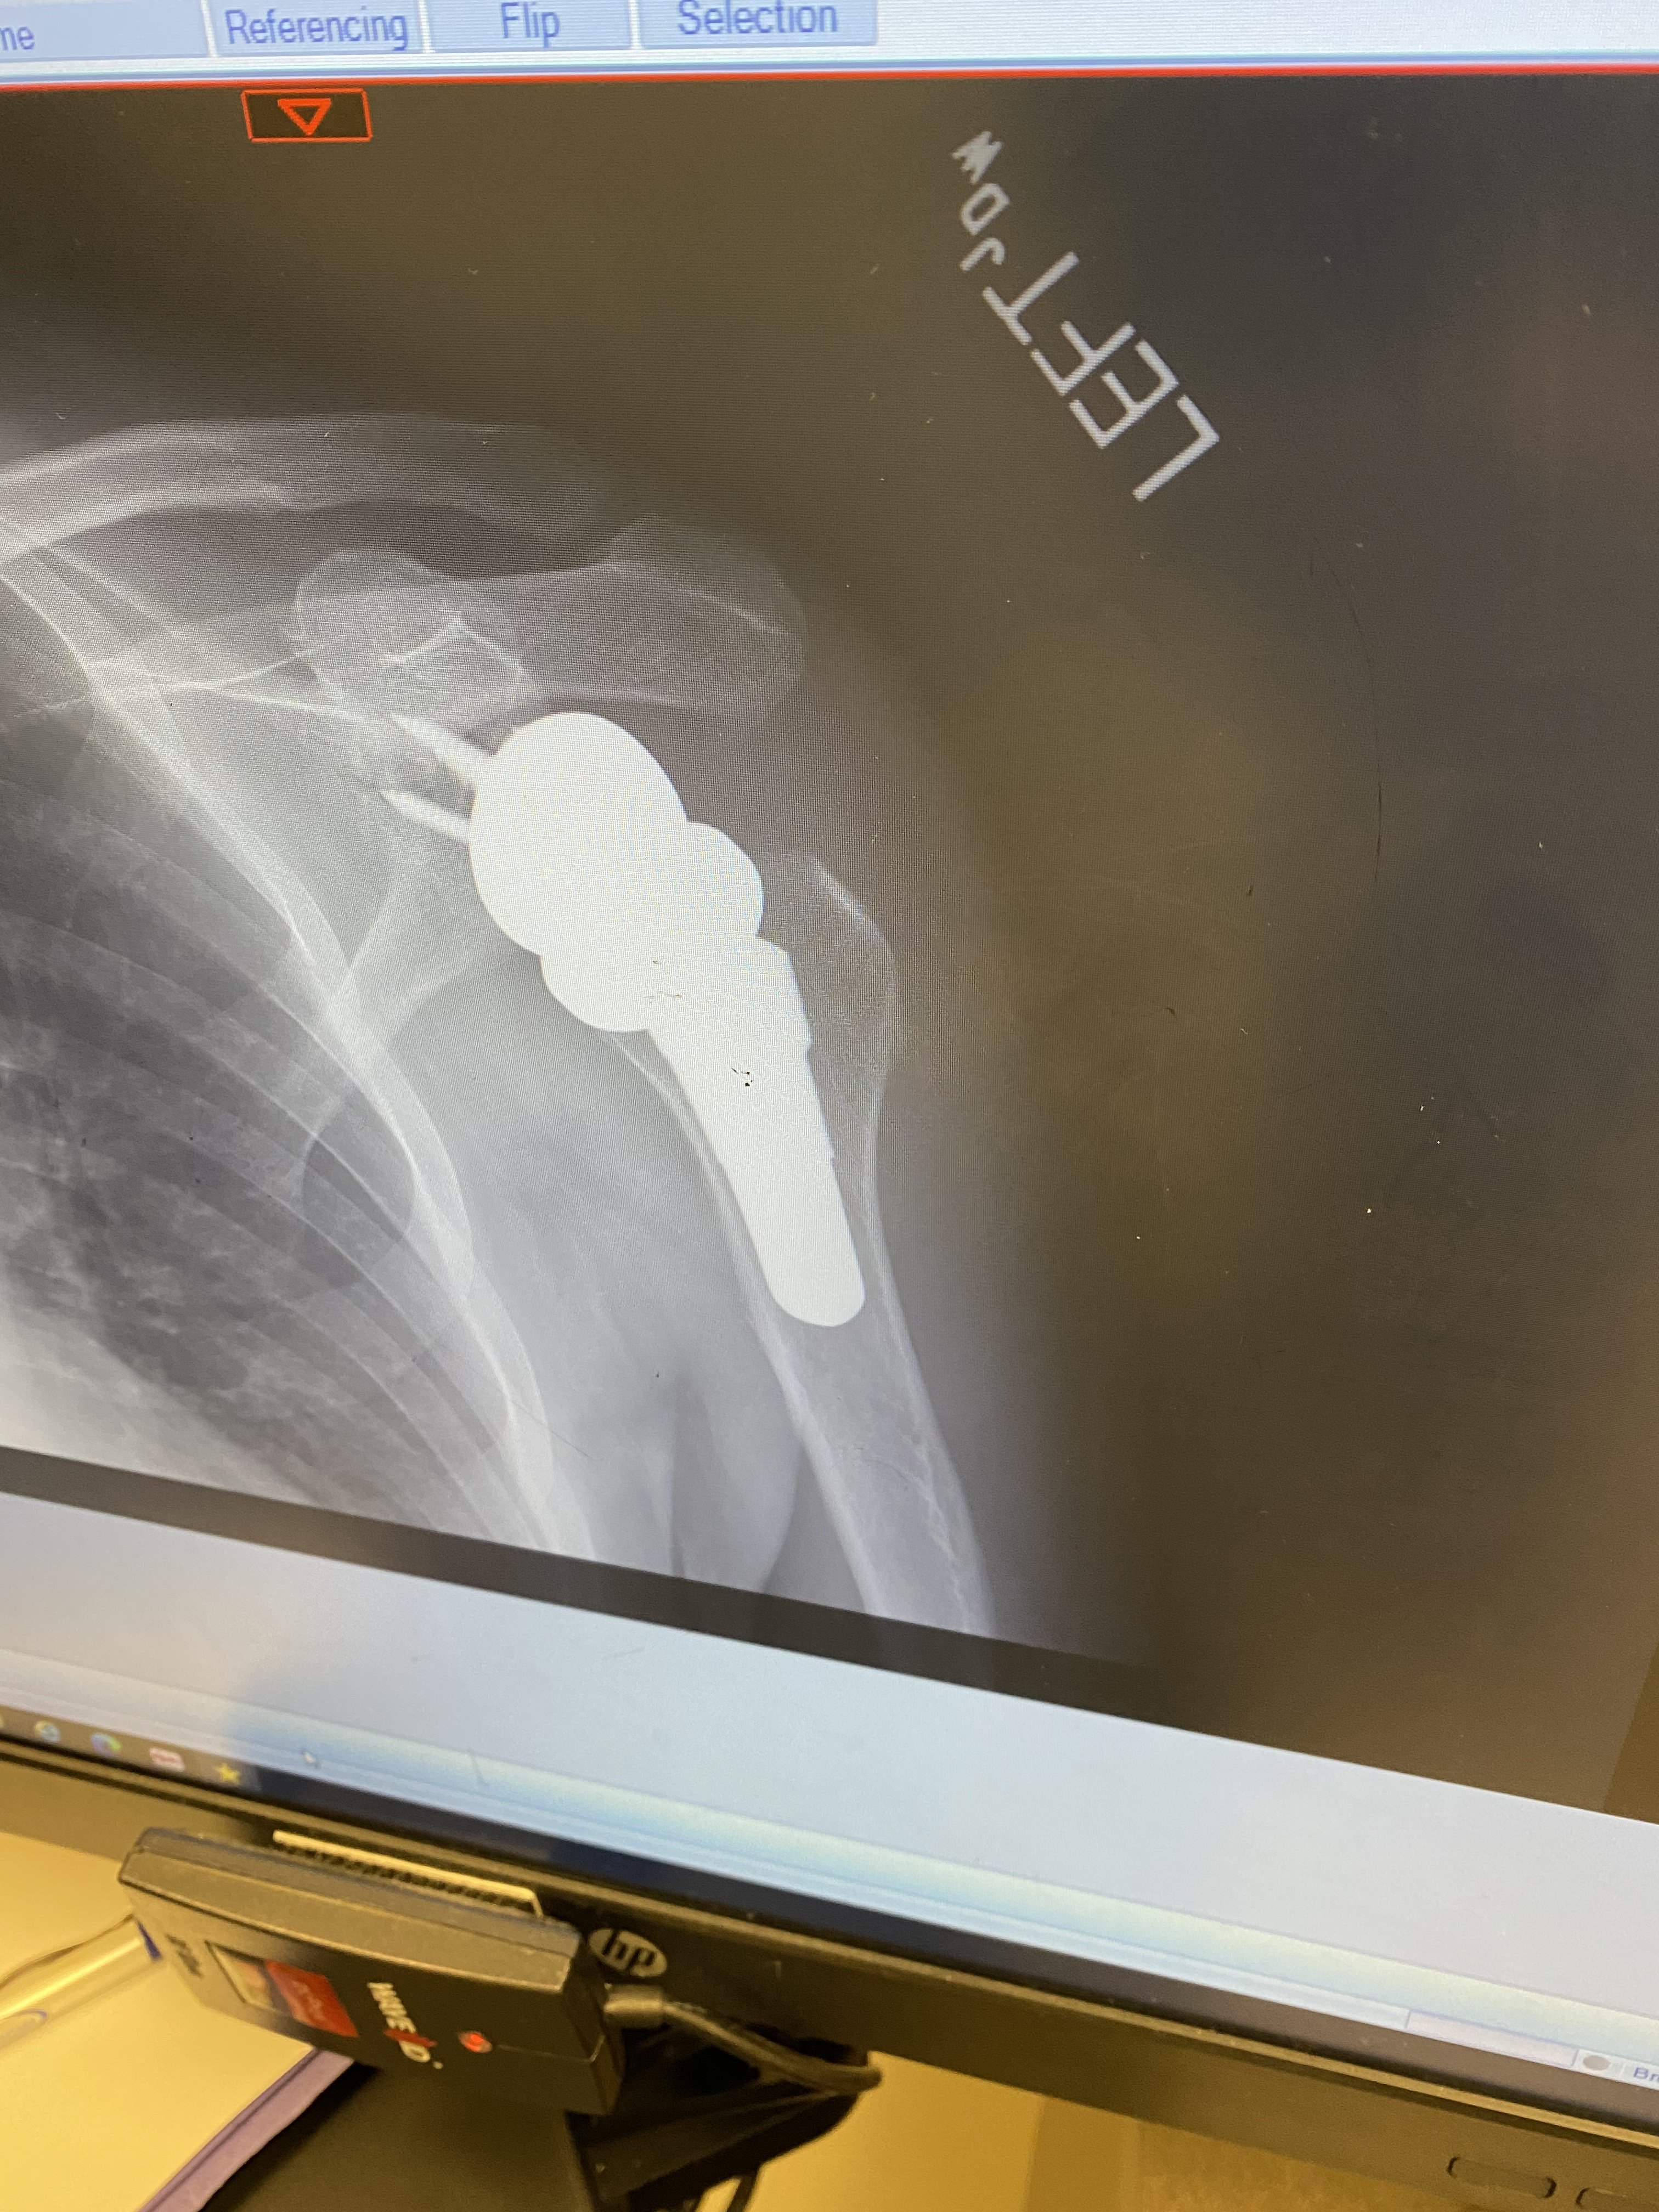

More X-Rays were taken today to confirm proper hardware alignment and this time I took screenshots of the computer when I was shown the pictures of my shoulder.

The next picture is after surgery showing installed hardware, the ball is now attached to the area of the shoulder blade and the cup is now on the upper arm bone.